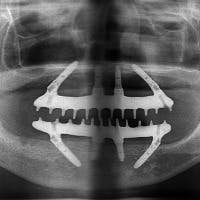

2011年国立大学歯学部卒業の歯科医師です。2018年歯科医院を開業して、2020年医療法人理事長に。インプラント治療を得意としており、All-on-4の症例を多くこなしています。